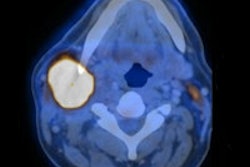

A French PET/CT study has revealed alarming gaps between radiation dose measured in different areas of the hand, calling into question the accuracy of radiation safety monitoring of staff, delegates learned this week at the Journées Françaises de Radiologie (JFR) congress in Paris.

The expansion of PET/CT and the growth in its indications pose a significant dosage problem due to the high energy (y = 511 keV) of radiation stemming from FDG, explained lead author Fabien Salesses and colleagues from the imaging division at Hôpital Haut-Lévêque, Centre Hospitalier Universitaire (CHU) de Bordeaux. Legislation on extremities dosage only exists in terms of nonobligatory recommendations, because thermoluminescent dosimetry (TLD) is not optimally adapted to nuclear medicine.